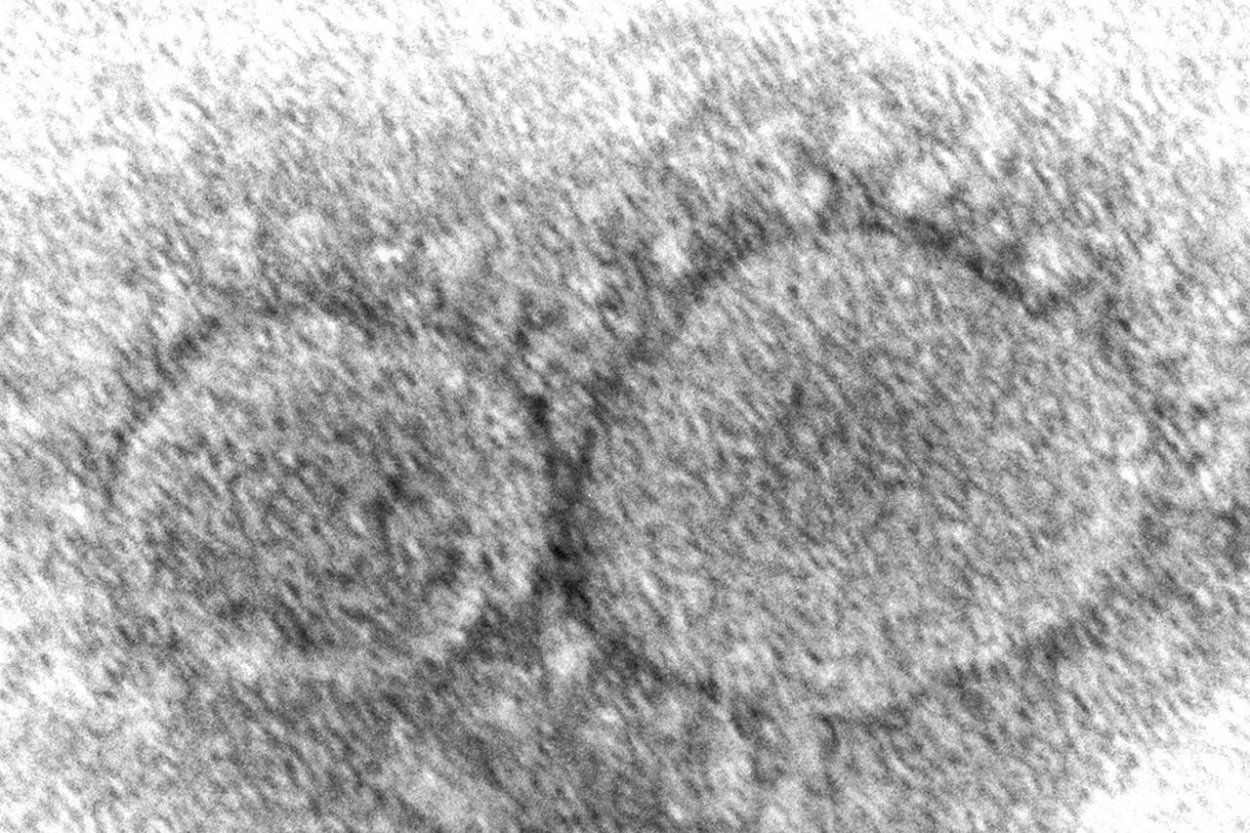

v Česku objavili prípady dvoch nových mutácií koronavírusu omikron označené ako BA.4 a BA.5. „V súčasnosti evidujeme dva záchyty BA.4 v Moravsko-sliezskom kraji. Zároveň evidujeme tri záchyty BA.5 z Juhomoravského kraja," uviedol český Štátny zdravotný ústav. Informuje o tom spravodajský portál TN.cz.

Experti z Európskeho centra pre kontrolu a prevenciu chorôb (ECDC) zmenili klasifikáciu týchto variantov koronavírusu z označenia „variant záujmu" na „variant hodný obavy". „Táto rekvalifikácia súvisí so vzostupom počtu prípadov v Portugalsku," vysvetlili odborníci z českého Štátneho zdravotného ústavu. Epidemiologická situácia v Česku sa však v súčasnosti zlepšuje z hľadiska počtu nových prípadov aj počtu hospitalizovaných pacientov.